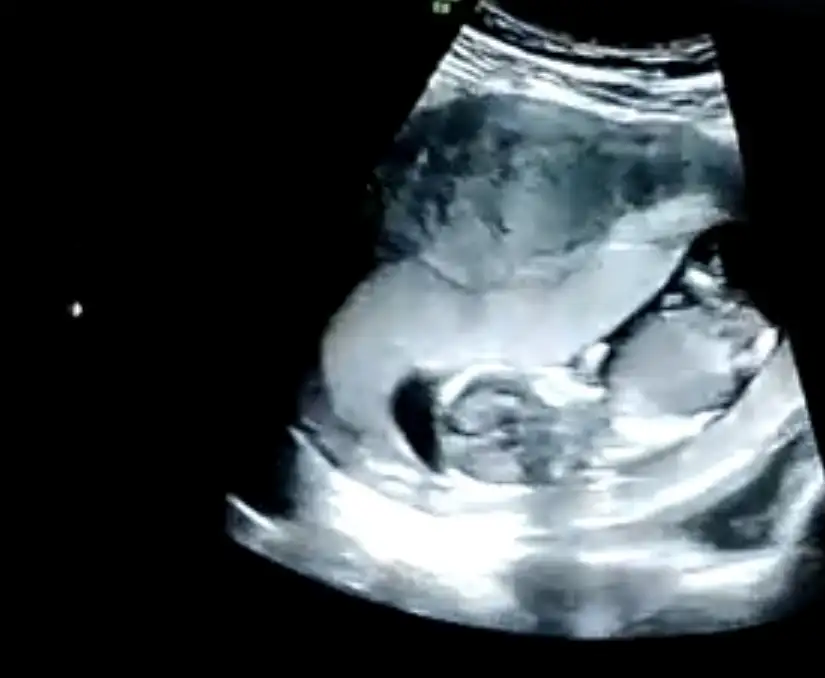

Ikra meyra Ikra meyra 13+1 haftalık karından ultrason görüntülerini yorumlayabilir misin?☺️🙏

Ikra meyra Ikra meyra tahminin doğru çıktı 16 hafta erkek demiştin doktorum kesin erkek elbiselerini bile al dedi ☺ değişir mi bilmiyorum ama atıyim bir bak

Artık erkektir canım 😍 sağlıkla gelsin oğlusun 🥰 anketim oylarsaniz sevinirim 😘